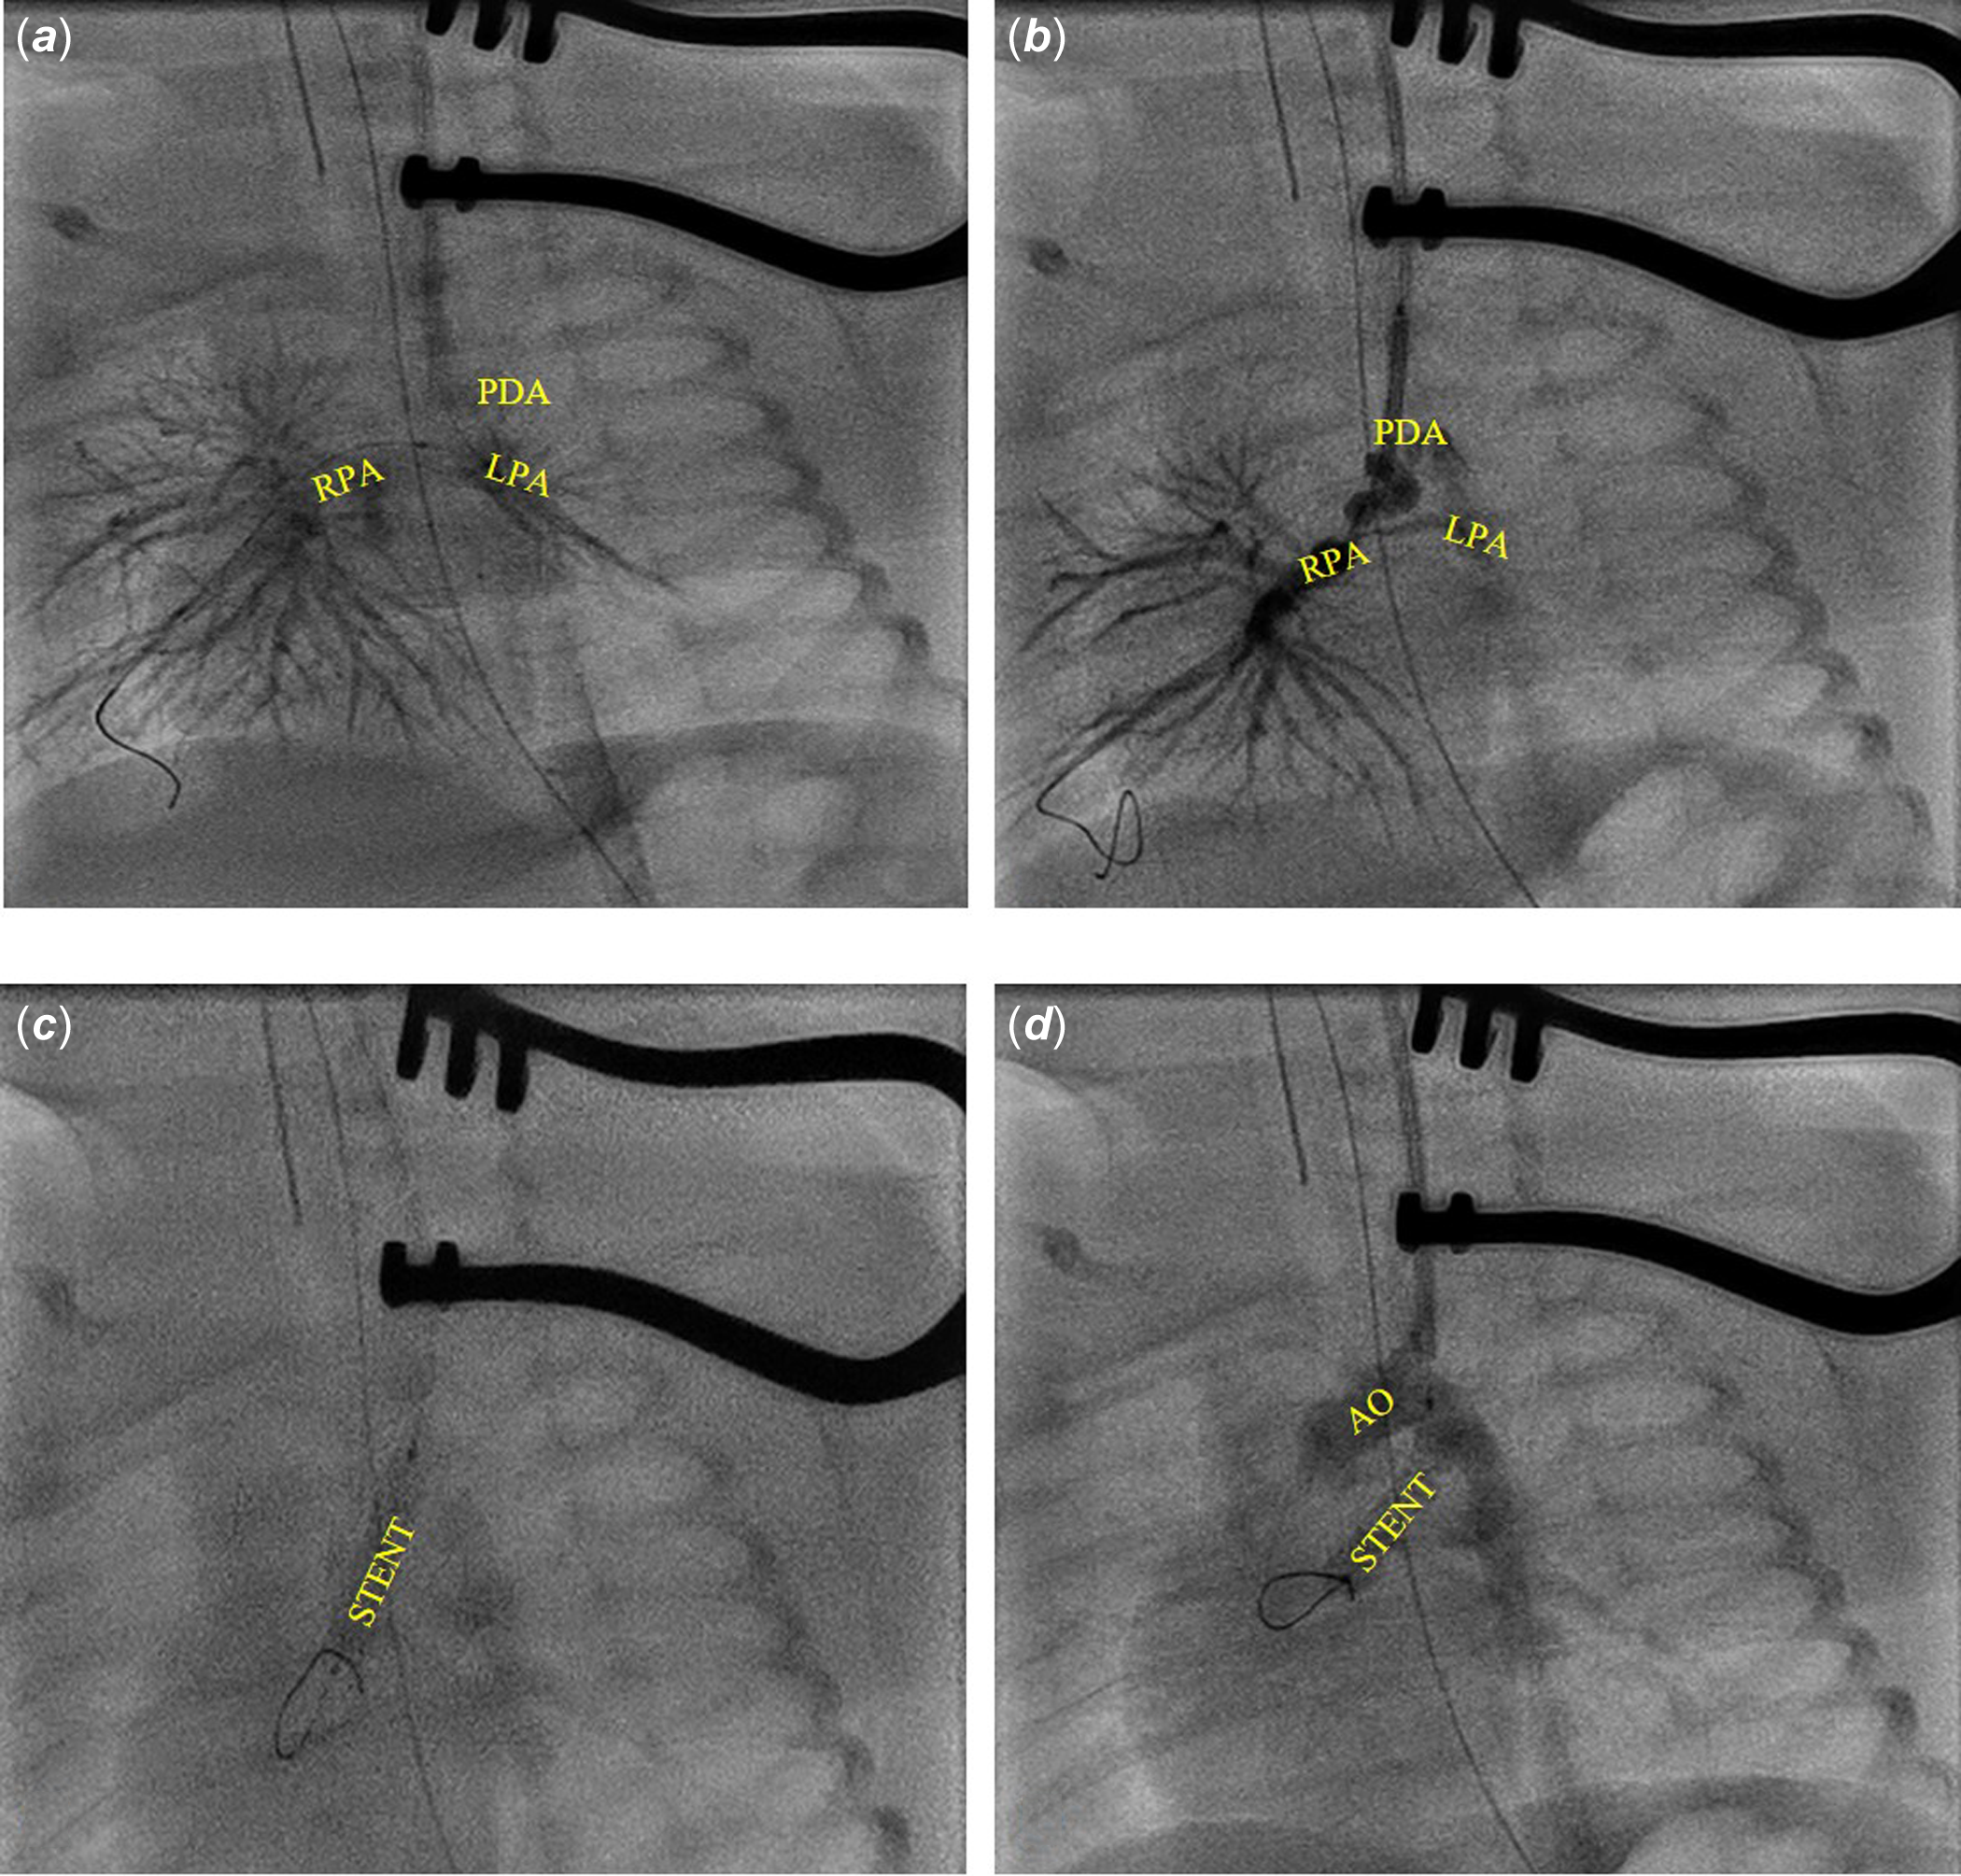

Under general anaesthesia after administration of antibiotic prophylaxis and un-fractioned heparin administration, through a surgical left carotid 4 Fr access, angiography was performed directly through the sheath to visualise the patent arterial duct. The fluoroscopy image confirmed echocardiographic findings: a tortuous patent arterial duct with a stenotic section in the third distal end (Figure 2). A MaverickTM (Boston Scientific, Marlborough, MA, USA) coronary balloon was advanced and inflated inside the duct to size the patent arterial duct length and to get straighten out the intricacies; however, it proved too short to cover the total patent arterial duct length. Thus, we first tried with a 4x24 mm bare coronary RebelTM stent. Unfortunately, during the positioning manoeuvres, the patent arterial duct changed deeply in shape and the stent resulted to be too long.

We removed the stent. Angiography from the sheath showed a widespread spasm of both pulmonary branches, and especially the left lung had not contrast enhancement as the right had and the patent arterial duct appeared to be curled on the stent.

Thus, a shorter (3.5x16 mm) bare RebelTM coronary stent placement was attempted. It failed due to the patent arterial duct morphology (patent arterial duct spasm associated to the tortuous anatomy). Finally, to improve the trackability and to make the patent arterial duct as straight as possible, we advanced a TorqVueTM LP 4 Fr catheter with a 2.7 Fr microcatheter, using the “mother in child” technique. Once the TorqVueTM LP catheter was in the left branch of the pulmonary artery, the 3.5x16 mm RebelTM coronary stent was advanced in the catheter and successfully deployed. Final angiography was performed by using the same TorqVueTM LP catheter.

Figure 2. A. Angiography by the left carotid access. B. 3.5x 24 RebelTM stent protruding in left carotid and the PDA curled on the stent. C. 3.5x 16 mm RebelTM stent deployment. D. Angiography after the 3.5x16 mm RebelTM stent deployment. AO = aorta; PDA = patent ductus arteriosus; RPA = right branch pulmonary artery; LPA = left branch pulmonary artery; STENT = stent.